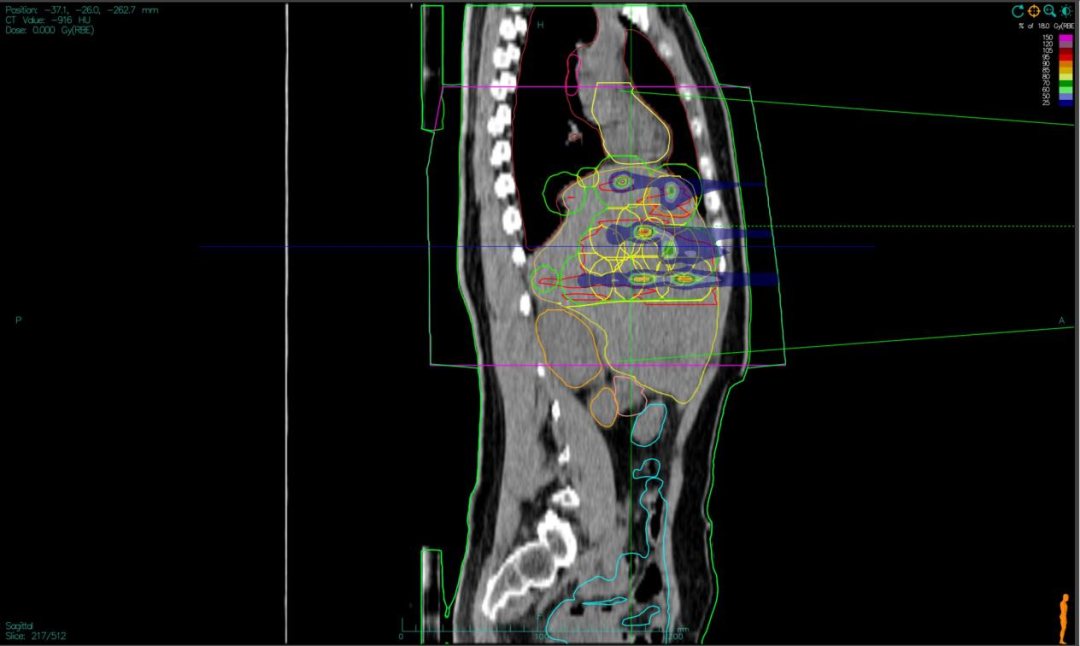

“双布拉格”,并非指代两个物理峰值,而是两大核心治疗理念的深度碰撞与融合。第一个“布拉格”,是物理学范畴的布拉格峰——重离子束流可在体内特定深度释放绝大部分能量,这一特性构筑起“指哪打哪”、极致保护正常组织的物理基石。第二个“布拉格”,是免疫学范畴的布拉格治疗,即国际前沿的PRaG协同治疗方案。它通过精准放疗在局部“点火”,释放肿瘤抗原;以GM-CSF为“导航”,引导免疫系统识别肿瘤细胞;再借助PD-1抑制剂“解除免疫刹车”,让免疫细胞能够持久、全身性地攻击肿瘤,最终追求珍贵的“远隔效应”。而晶格放疗,正是连接两大“布拉格”理念的关键桥梁。针对常规手段无法照射的巨大肿瘤,它将均匀剂量场转化为无数离散的高剂量“能量岛屿”。这种模式不仅能奇迹般保护穿插其中的正常组织与脉管结构,其独特的剂量分布,更被证实可高效诱发免疫原性细胞死亡,将物理打击的能量,转化为激活全身免疫反应的“信号”,让肿瘤的局部治疗与全身控制成为现实。

四大优势协同发力:一,依托重离子射线特有的“布拉格峰”物理特性,实现对深部肿瘤的“定点爆破”;二,采用“晶格放疗”先进布野技术,在巨大肝肿瘤内部精准布设能量“棋盘格”,在高效杀伤肿瘤细胞的同时,为残存正常肝组织与关键脉管留存生存空间;三,将此次精准物理打击,完美嵌入“布拉格治疗”免疫协同策略,以此作为激活全身免疫反应的“点火器”,联合PD-1抑制剂与GM-CSF,力求激发远隔效应,对未被照射的病灶形成攻击;四,引入干细胞支持下的新一代免疫细胞疗法,整合诱导多能干细胞(iPSCs)或间充质干细胞(MSCs)来源的免疫效应细胞(如CAR-T、CAR-NK和TCR-T细胞)与工程化技术,提升癌症免疫治疗的可及性与疗效。